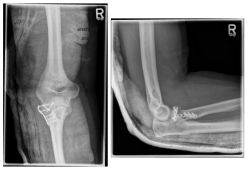

Ellenbogen3

Photo: The fracture on the left is after an operation with a plate and screws